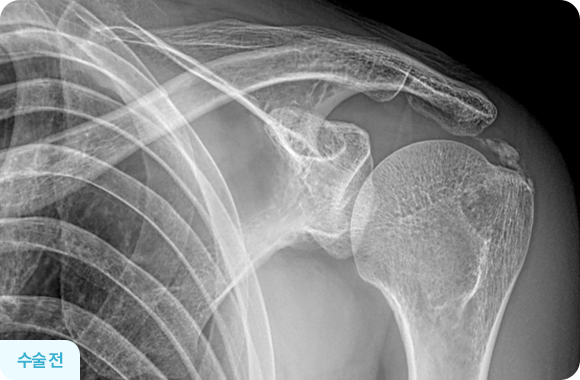

관절경을 이용한 석회제거술 전